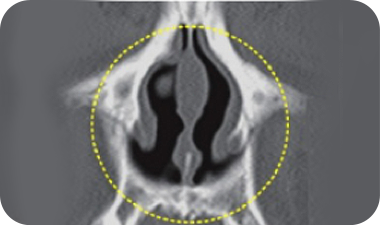

鼻中隔弯曲症C型的矫正范围

鼻中隔弯曲症S型的矫正范围

鼻中隔弯曲症

鼻中隔是指垂直于中央位置的轴线,分割两侧鼻孔的隔膜。

这种鼻中隔弯曲或扭曲的情况被称之为鼻中隔弯曲症,根据鼻中隔的弯曲情况,分为C型及S型两种形式,是一种可引起鼻塞,鼻炎及鼻窦炎等功能障碍的生理性原因。

手术技术

根据鼻中隔弯曲的状态去除弯曲部位的鼻中隔软骨,并利用剩下的鼻中隔软骨矫正鼻尖形状及高度。

手术前

弯曲的鼻中隔

手术后立即

被矫正的鼻中隔